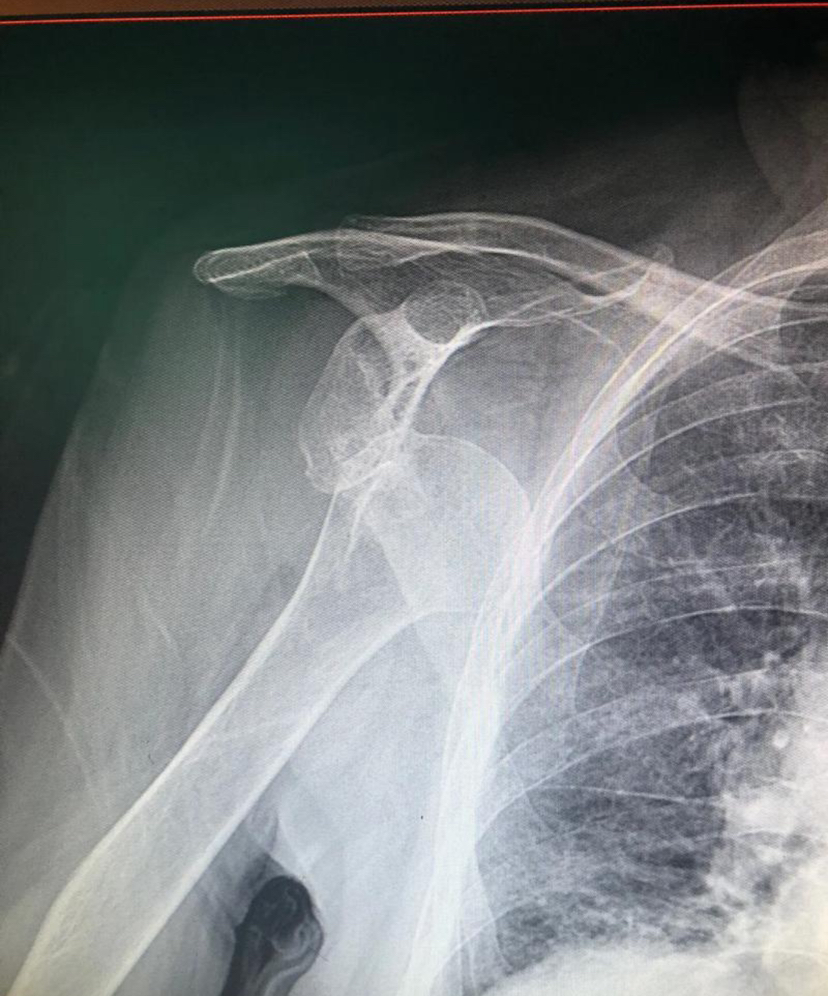

2008年,Griffith的研究发现,在首次前脱位的患者中,肩胛盂骨丢失的发生率为41%,而再次脱位的患者中,发生率高达86% ,初次肩关节脱位患者中肱骨头骨缺失的发生率高达 81%.Olds等人2015年一项系统评价和荟萃分析,1324 名患者,再次脱位率高达 39%,研究认为,年龄小于40岁、男性以及韧带松弛是再次脱位的高危因素。2019年,Dickens等对714名运动员进行为期 4 年的前瞻性队列研究,其中 22 名运动员首次出现前向不稳定事件,作者发现,在首次脱位后,测量肩胛盂骨质流失量6.8%,而在复发脱位后,计算得出的肩胛盂骨质流失总量为22.8%。

2025年7月,比利时肩肘外科协会94名医生共识,最重要的危险因素为:肩胛盂骨缺损;其次重要的危险因素为:1.肱骨头缺损2.从事投掷运动或接触性运动的患者3.肩胛盂轨迹(脱轨);再次重要的危险因素为:年龄(年轻患者)。

基于以上证据,对于年龄< 40岁、活动量大(运动员、军人等)、肩胛盂骨缺损、肱骨头缺损、男性、多发韧带松弛 的患者,建议初次脱位后积极行手术治疗。而对于年龄> 40岁、低活动需求、无结构性损伤 的病人,首选保守治疗。但无论是建议手术还是保守治疗,都需要与患者充分沟通、共同决策,且康复训练不可忽视。